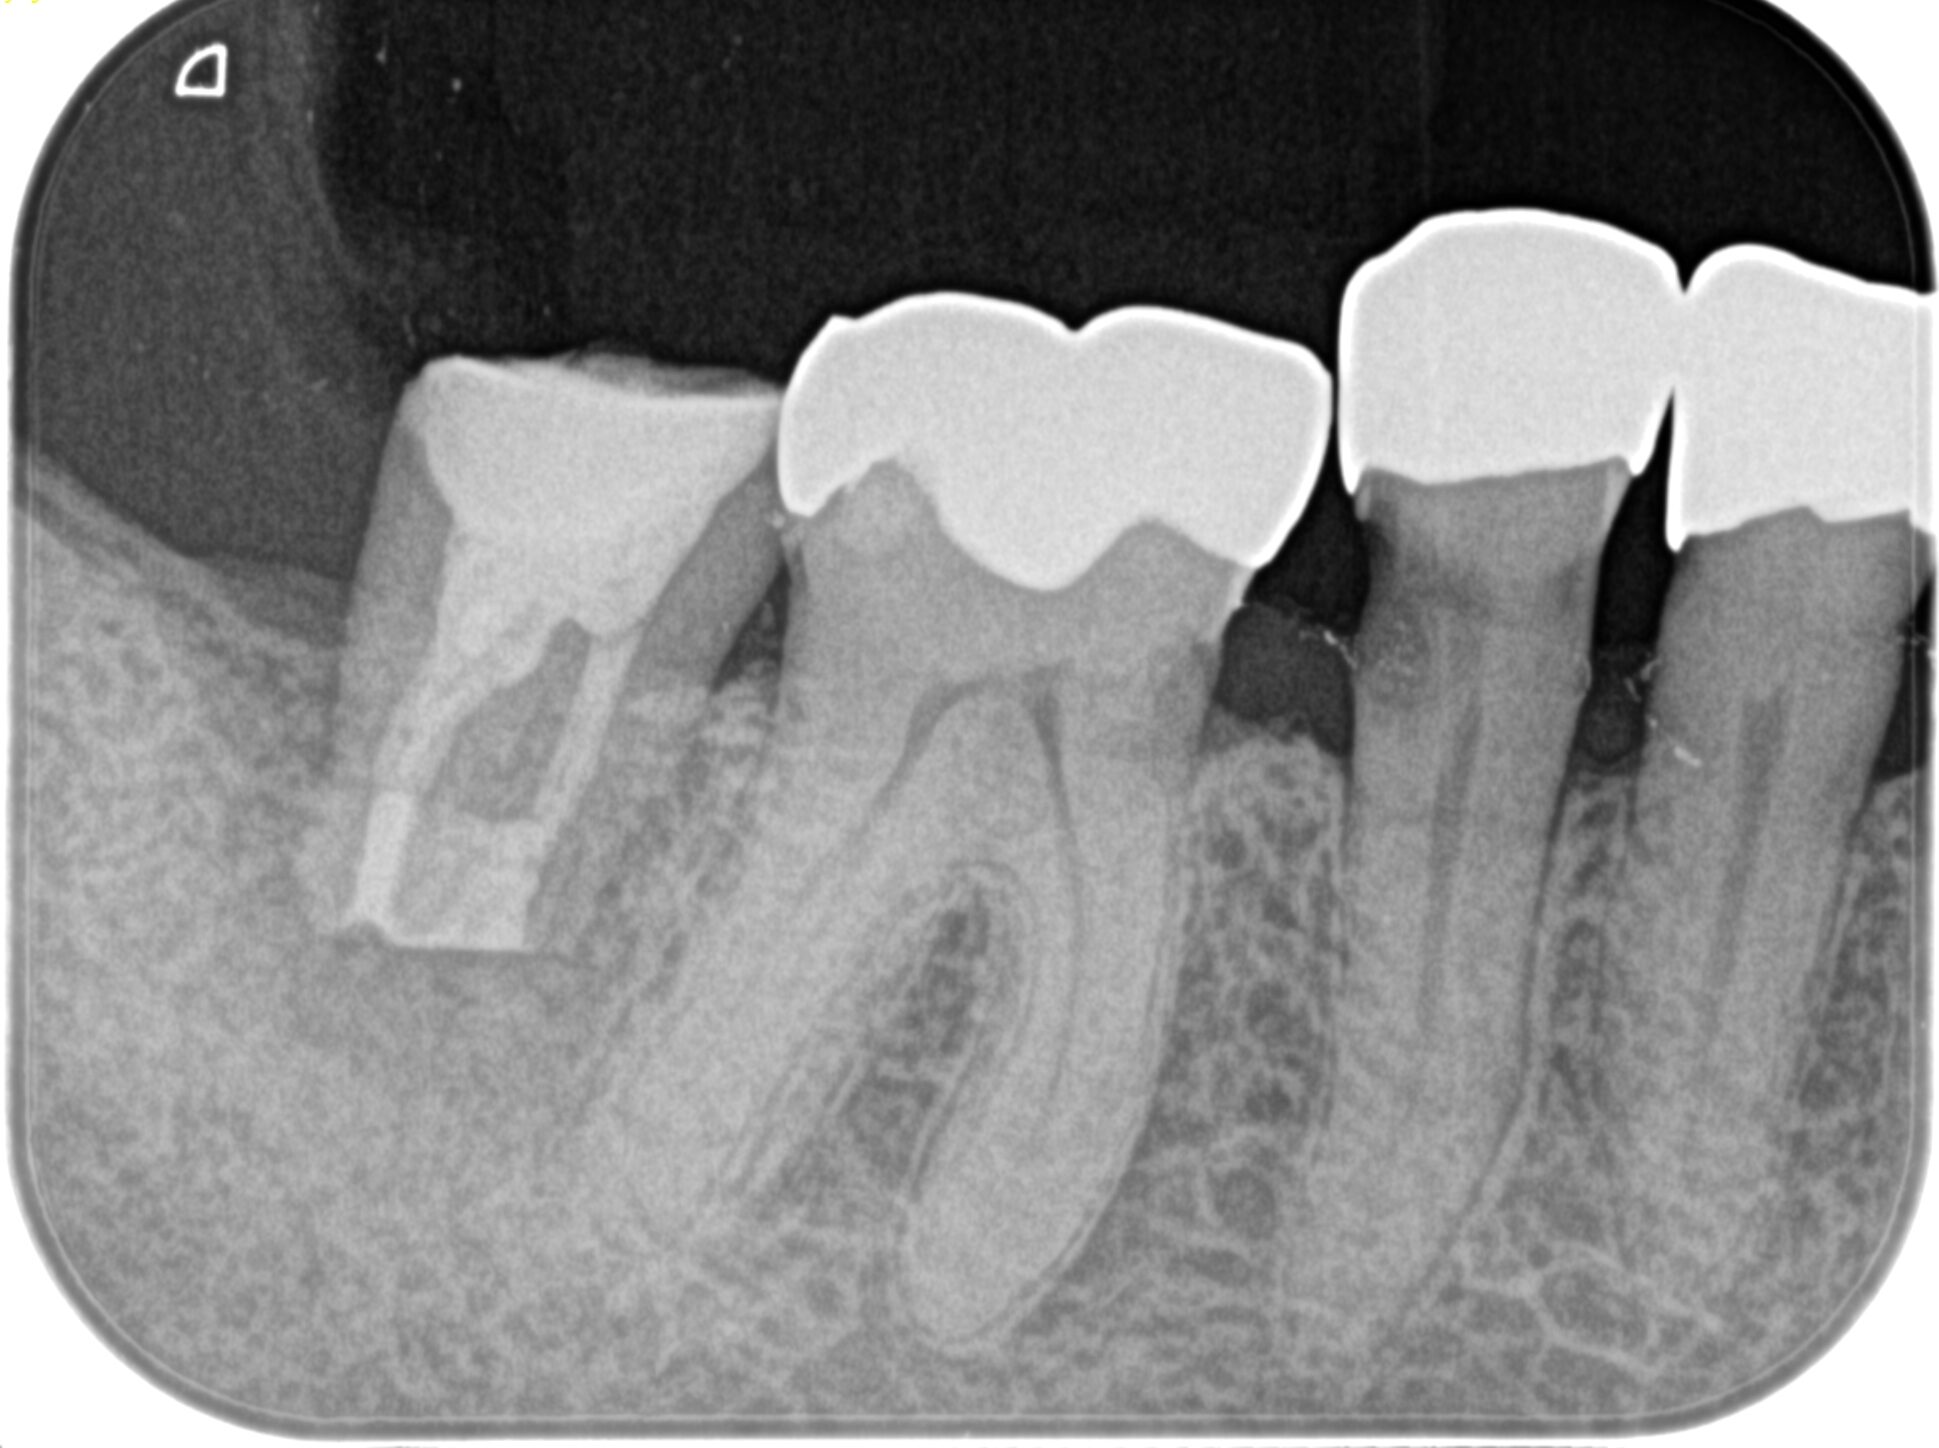

#31 Intentional Replantation 6M recall(2025.11.20)

歯牙の動揺も、

頬側の歯周ポケットも消失した。

術前の臨床症状もない。

ML

MB

D

初診時と比較した。

初診時の絶望的な状況から改善されている。

最終補綴もOKと言えるだろう。

結論を言えばこの歯周ポケットはエンドが作ったものだったのだろう。

が、エンド病変が治癒したらそれが改善されている。

エンド→ペリオ病変であったと言うことだ。